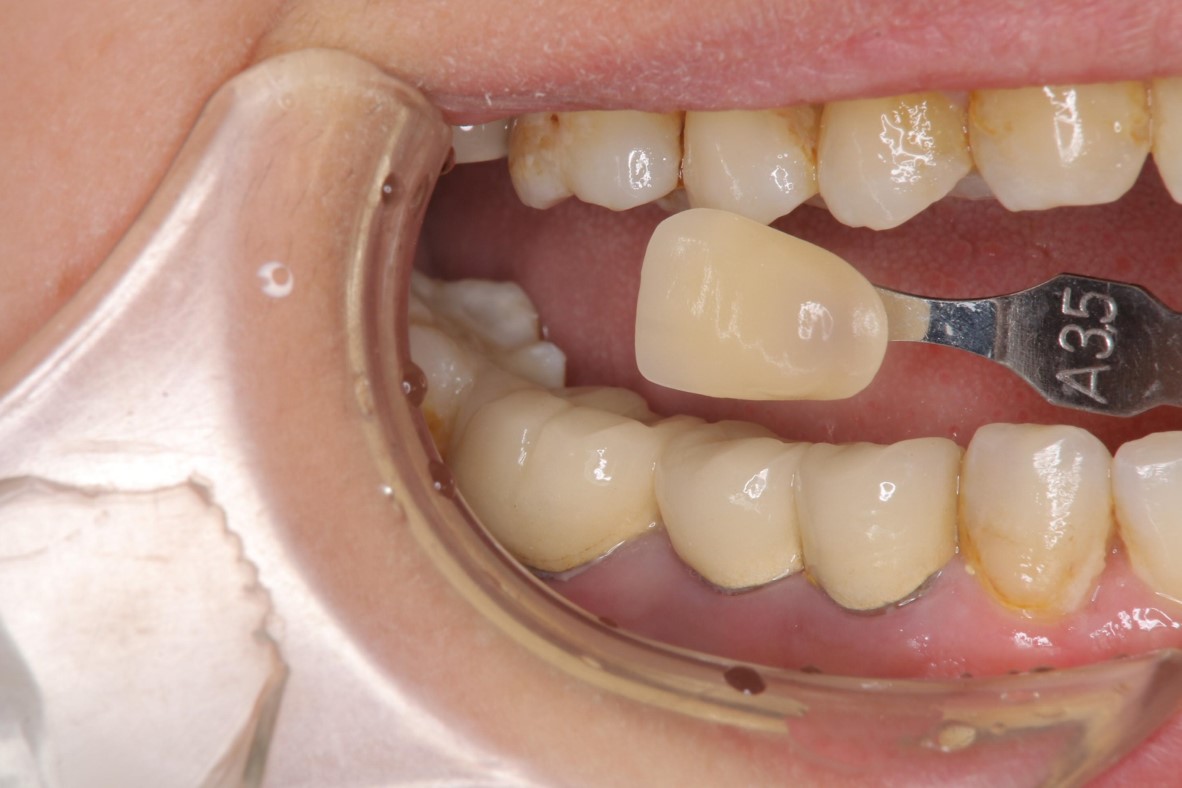

照相比色